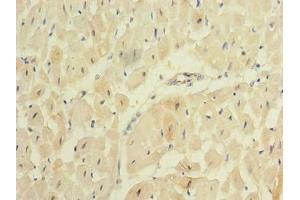

Choisissez l’un des 34 anticorps REEP2 de notre liste de produits basés sur 16 images de validation.

Découvrez des anticorps REEP2 fiables issus d’une large sélection de fabricants renommés. Notre portefeuille permet une détection précise de REEP2 dans plusieurs espèces, y compris Human, Mouse, Rat, Dog, Horse, Rabbit, Cow, Guinea Pig, et prend en charge diverses applications de recherche telles que WB, IF (cc), IF (p), ELISA, IHC (p).